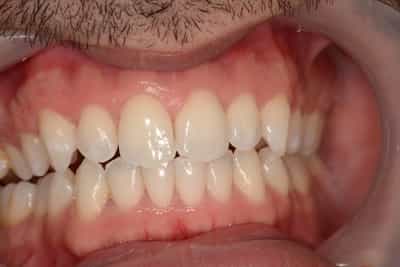

Cas numero 2 :

Cas terminé